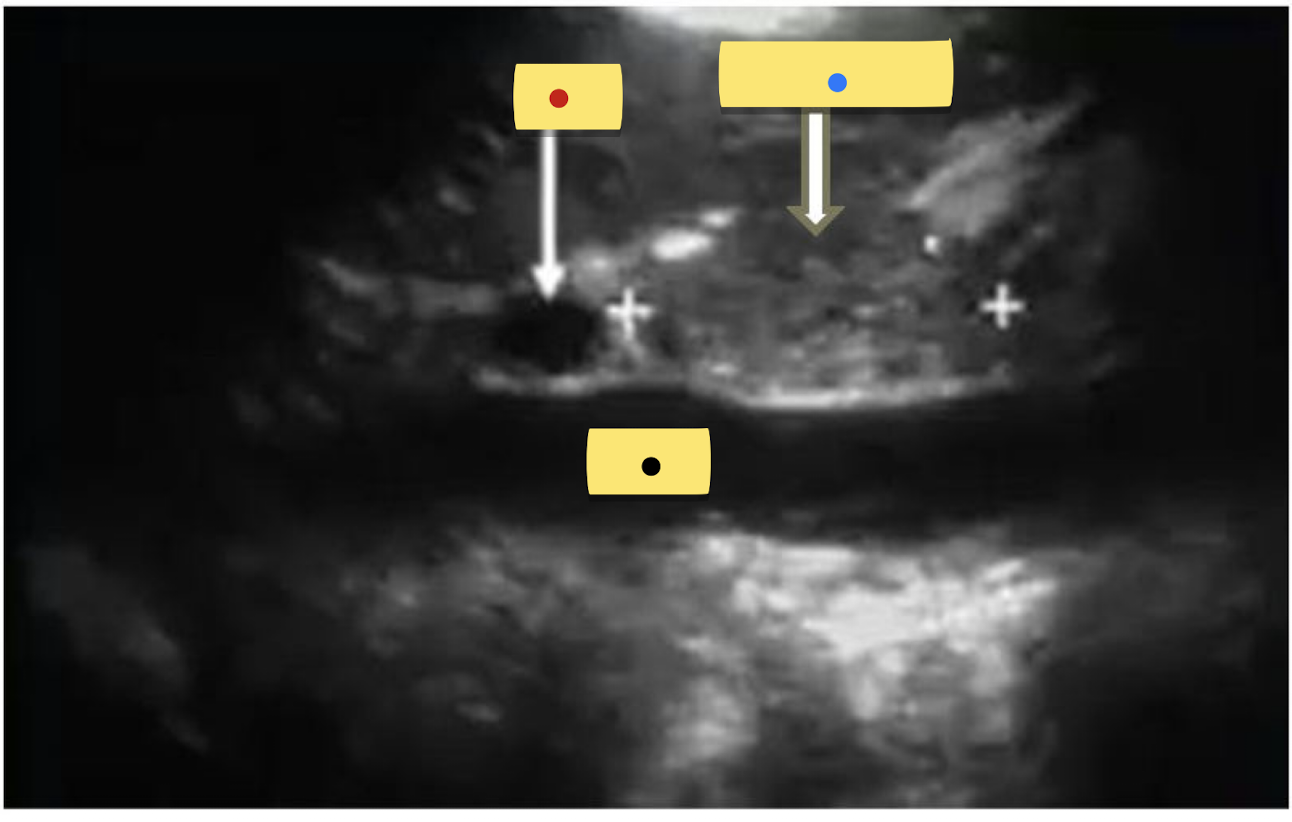

identify the sagittal image.

Red = ?

Blue = ?

Black = ?

Red = MPV

Blue = pancreatic Head

Black = IVC